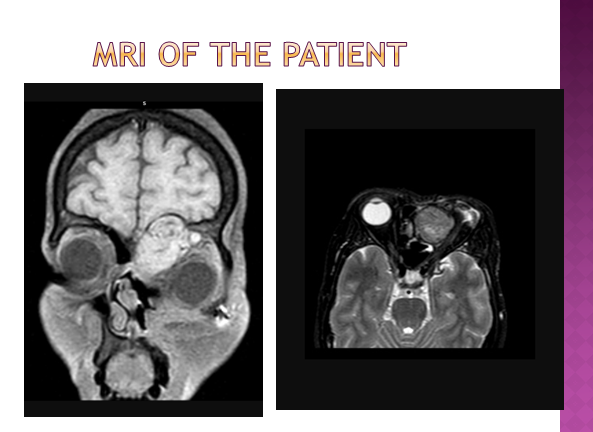

Shruti Gohel: Latest MRI of the patient

Shruti Gohel: I will upload the films today once I get to the department of the Radio diagnosis.

Dr. Rakesh: The MRI https://blogger.googleusercontent.com/img/b/R29vZ2xl/AVvXsEis-QZVuw5S_EpNaflYrNsIjDxYwnIgo3bfo0j4AE1DUPtoMOPBLSJPSuoOWKVlqKF1knTAENI2Jim1LsXvALPzaLKh4zkpQdxeNJrTn1yCSkvcoVMH_P7g4oA-4VMtFjAkkQzo_jllPLvN/s1600/she+401.jpg is very much suggestive of a recurrence. Looks like the end of the road for her? Any suggestions? (Amy, Kaustav, Bhavik, Prakhar)

Dr. rakesh: Thanks Shruti, the images suggest approximately similar growth size as in the previous recurrence? Heartening to see that she may get the procedure she needs. Wish this time we could do something better to prevent the next recurrence.